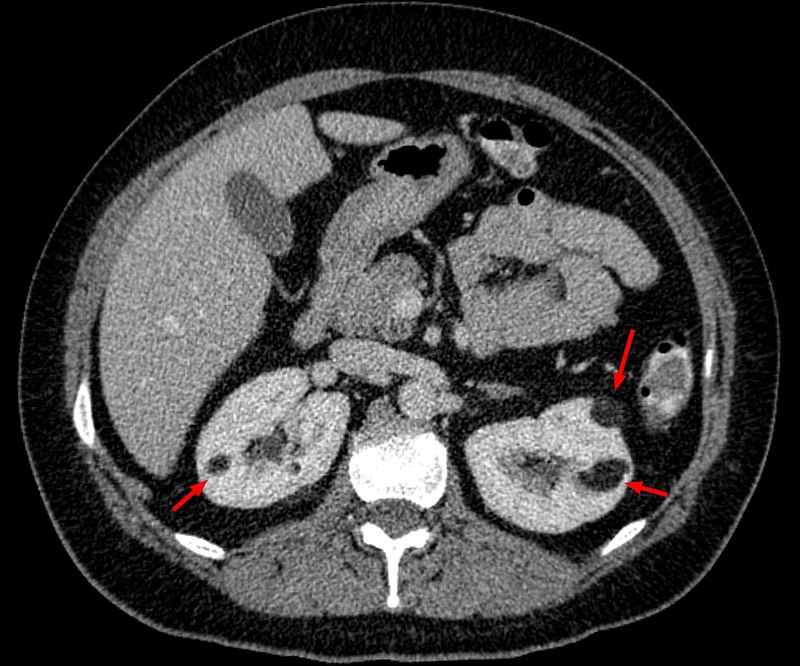

Renal Cell Carcinoma (RCC)

Renal cell carcinoma (RCC) is a malignant cancer cells are located in the lining of kidney tubules, which are incredibly tiny tubes. This condition is known as renal cell carcinoma.

When examined under a microscope, the most common variant of renal cell carcinoma shows clear cytoplasm or a clear cell type.

Loss of the tumor suppressor gene VHL causes an increase in the growth-promoting hormone IGF-1 and the transcription factor HIF, which in turn causes an increase in the growth hormones VEGF and PDGF.

Renal cell carcinomas (RCCs) may be hereditary or sporadic.

Risk factors for sporadic renal cell carcinoma (RCC) includes:

- Male

- Age of 60 or older

- Smoking

Hereditary renal cell carcinomas (RCCs) typically develop in younger adults and are bilateral.

The autosomal dominant illness known as von Hippel-Lindau disease increases the risk of renal cell carcinoma (RCC) and cerebellar hemangioblastoma by inactivating the VHL gene.